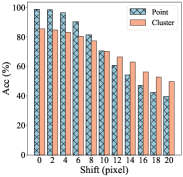

In clinical practice, due to the time constraint, pathologists cannot exactly put the annotation point at the center of a nucleus. We carry out experiments to investigate the impact of point perturbation to segmentation performance. To simulate the actual annotations, we perform a uniform random shift within different ranges of the generated point annotations. Several examples are shown in Fig. 5 illustrating that the small shift makes the points not too far from the center, but there are still some cases that the points are close to the boundary or even outside the nuclei. The number of points falling outside of the nuclei increases as the shift increases. Fig. 6(a) gives a quantitative illustration that as the shift increases from 0 to 20 pixels, the ratio of point annotations being within the nuclei decreases from 98.66% to 39.54%. Obviously, the offset of the points reduces the quality of the coarse labels, especially the accuracy of the nuclei in cluster labels is reduced from 85.46% to 49.72%. We train the models with the point annotations obtained by different shifts and calculate two object-level metrics. As illustrated by the changing trends of and AJI versus the shifts in Fig. 6(b), the segmentation accuracy of the proposed method degrades more gradually than that of the cluster results. The four-pixel shift only result in 1.38% drop in and 1.15% drop in AJI to the segmentation results of the proposed method, but 2.75% drop in and 3.27% drop in AJI to the cluster results. Even though the eight-pixel shift makes about one fifth point annotations not in the nuclei, the segmentation performance can still reach 70.75% in and 50.72% in AJI, respectively, which verifies the robustness of our method to point annotation offset. We believe that the robustness owes to the label propagation which refines the coarse labels to compensate for the impact of the offset. In clinical practice, professional pathologists will ensure the quality of point annotations, thus avoiding performance degradation caused by excessive offset. Some nuclei instance segmentation results with different shifts of point annotation are presented in Fig. 8. The robust instance segmentation performance lays the foundation for further counting and morphological feature extraction of nuclei on pathology images.